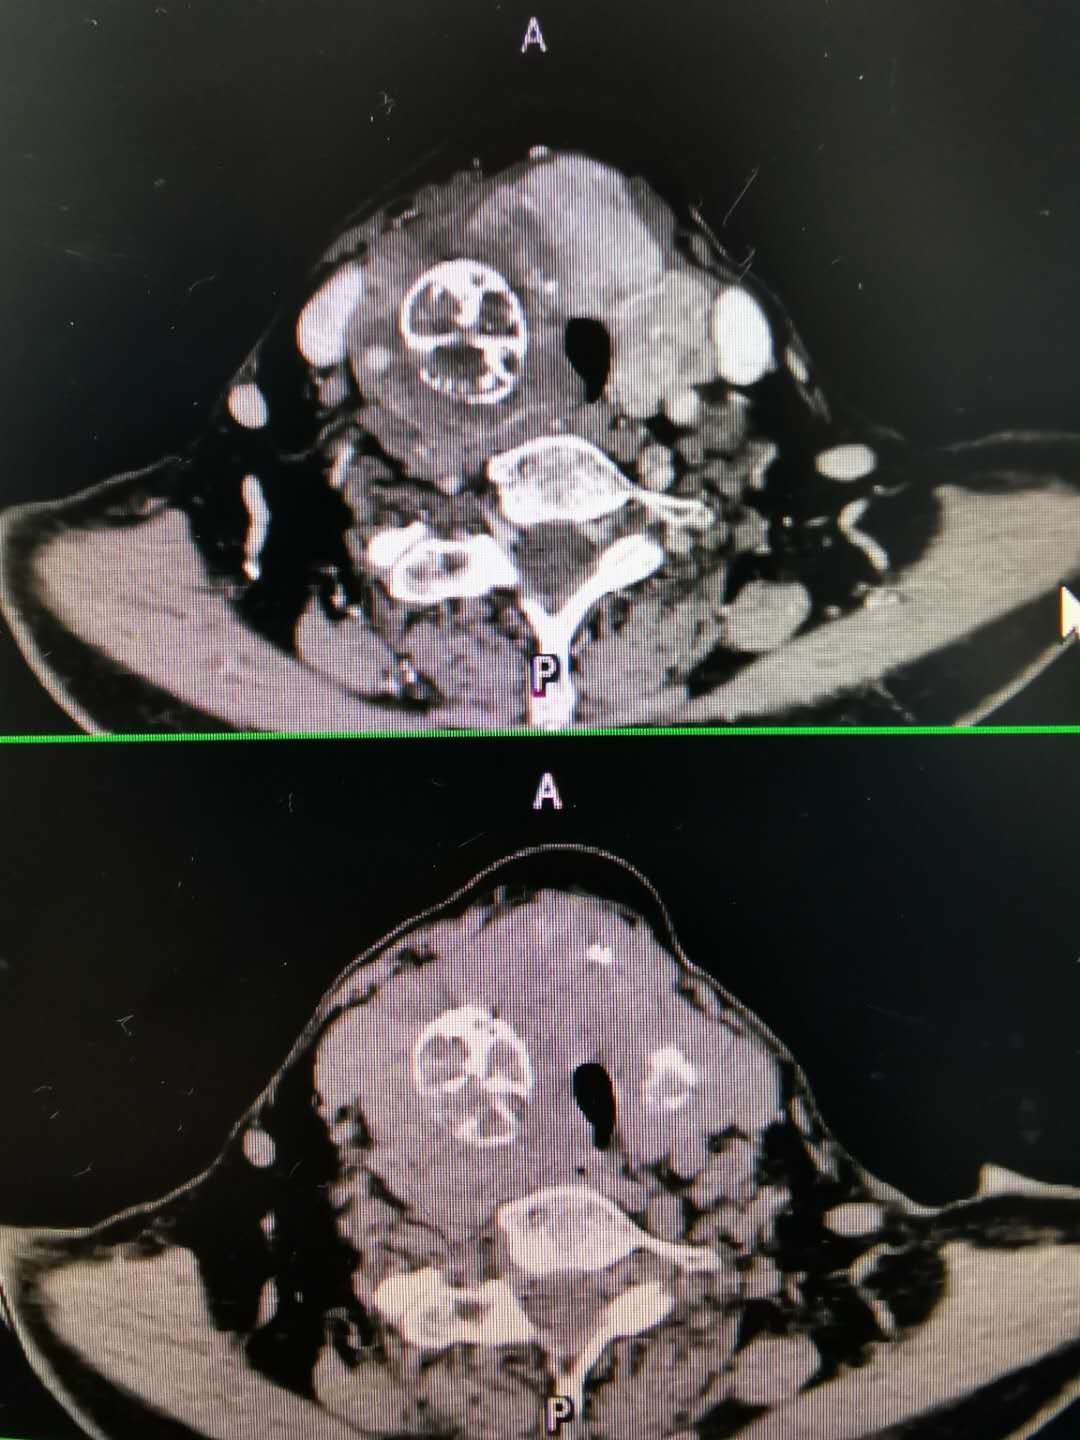

甲状腺良性肿瘤恶变甲状腺未分化癌1例原创